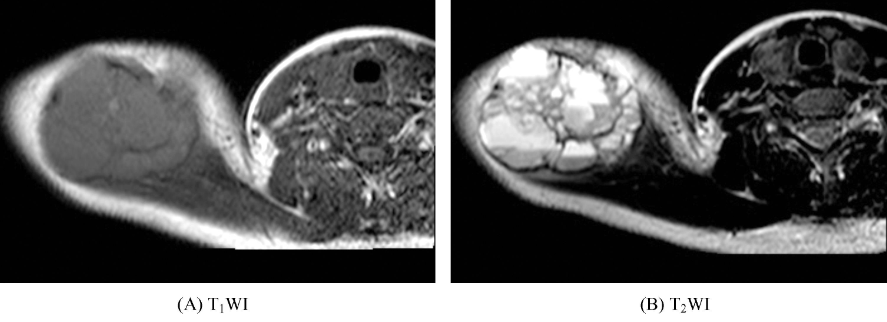

十、骨囊肿

好发于长管状骨干骺端的松质骨或骨干的髓腔内,多位于中心,一般为单囊,少数为多囊。表现为圆形或卵圆形的长T1、长T2信号影,周边可有一低信号的硬化环(图10),增强扫描无强化。邻近皮质可膨胀变薄,但其膨胀程度一般不超过干骺端宽度,病变长轴与骨干平行。一般无骨膜反应。骨囊肿可发生病理性骨折。

图10 骨囊肿左侧髂骨内见类圆形长T1、长T2信号影,边界清晰,见低信号硬化缘。